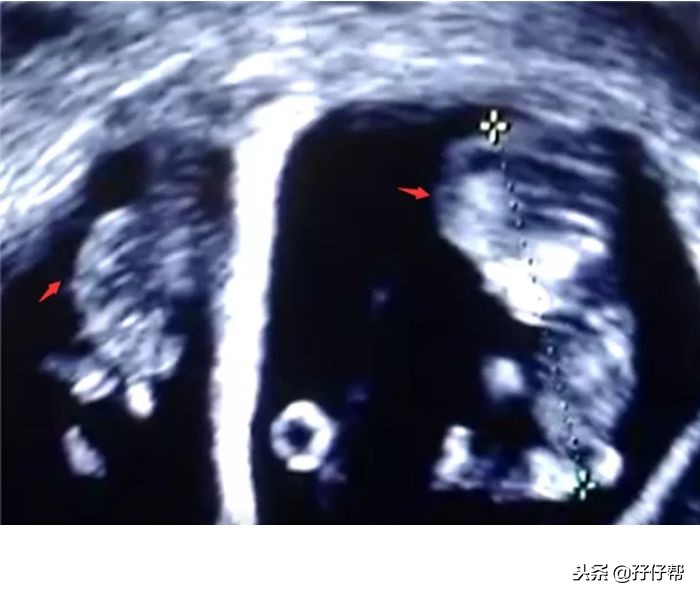

B超孕10周的双胞胎胎儿影像图⏬⏬: